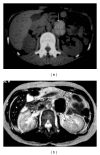

Non-Hodgkin and Hodgkin lymphomas frequently involve many structures in the abdomen and pelvis. Extranodal disease is more common with Non-Hodgkin's lymphoma than with Hodgkin's lymphoma. Though it may be part of a systemic lymphoma, single onset of nodal lymphoma is not rare. Extranodal lymphoma has been described in virtually every organ and tissue. In decreasing order of frequency, the spleen, liver, gastrointestinal tract, pancreas, abdominal wall, genitourinary tract, adrenal, peritoneal cavity, and biliary tract are involved. The purpose of this review is to discuss and illustrate the spectrum of appearances of nodal and extranodal lymphomas, including AIDS-related lymphomas, in the abdominopelvic region using a multimodality approach, especially cross-sectional imaging techniques. The most common radiologic patterns of involvement are illustrated. Familiarity with the imaging manifestations that are diagnostically specific for lymphoma is important because imaging plays an important role in the noninvasive management of disease.